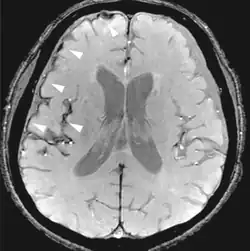

Fluid-attenuated inversion recovery FLAIR Fluid suppression by setting an inversion time that nulls fluids High signal in lacunar infarction, multiple sclerosis (MS) plaques, subarachnoid haemorrhage and meningitis (pictured).[15]